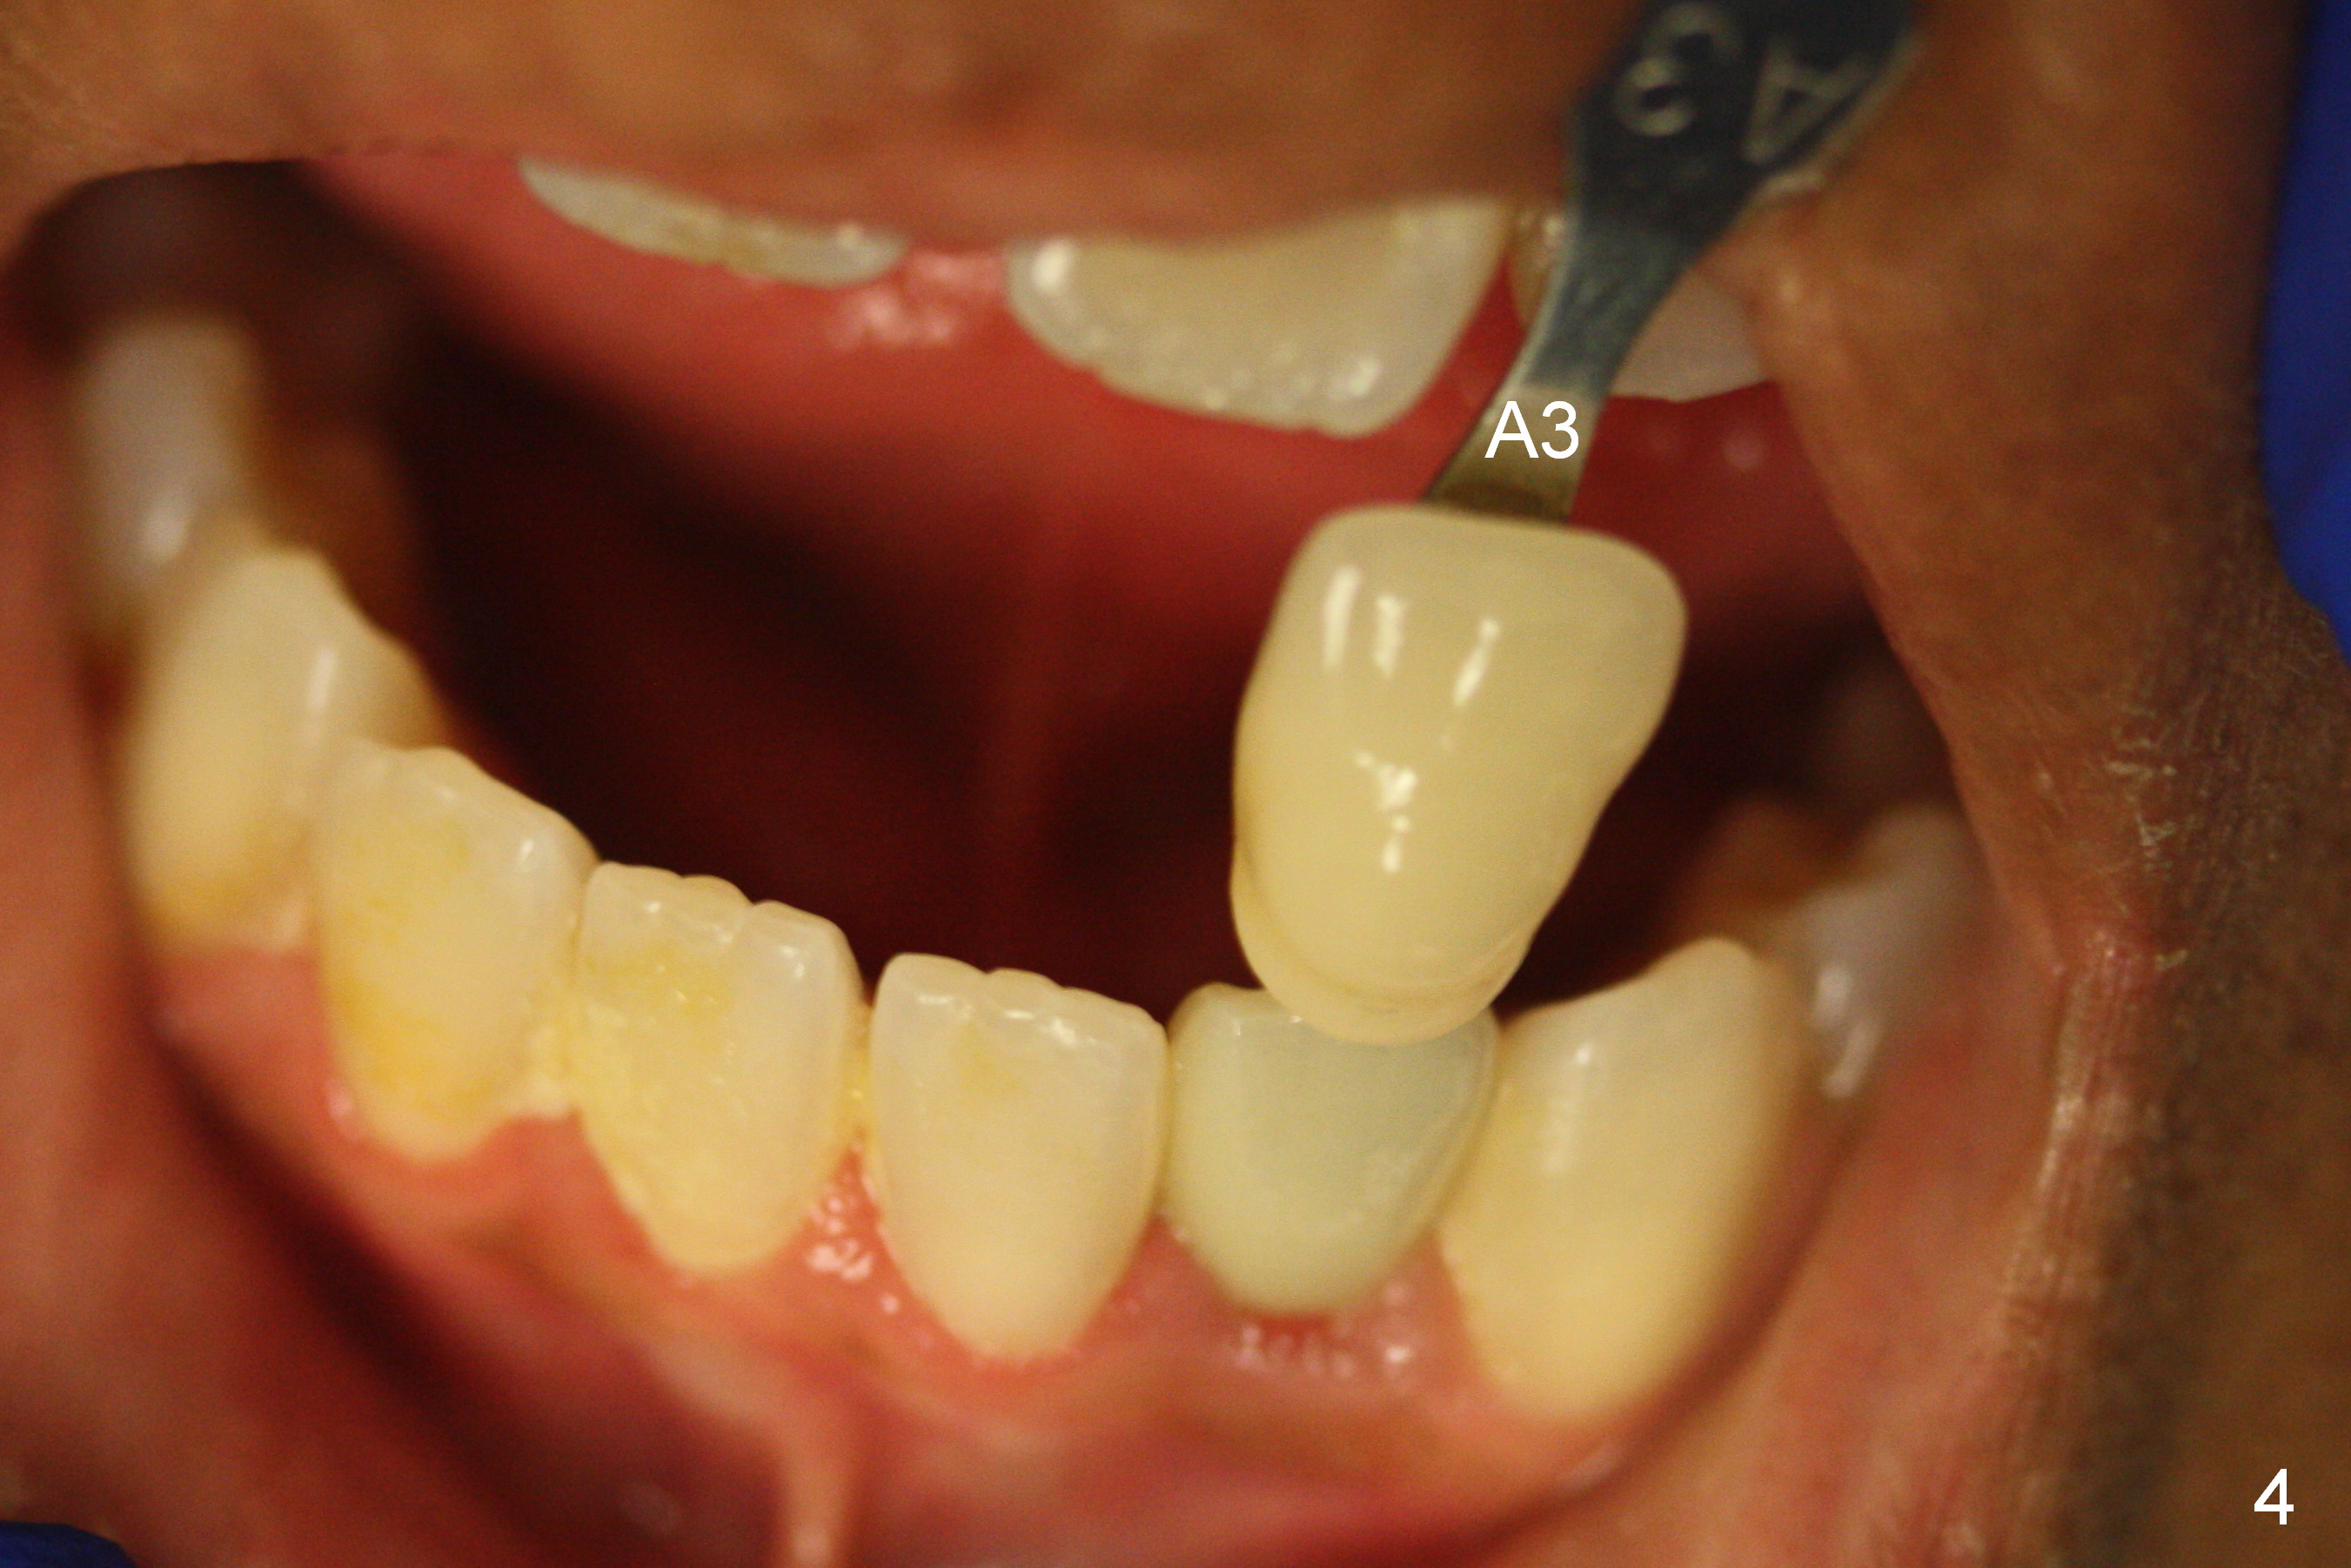

Choose a shade a little darker and more yellowish (Fig.4-7 before

cleaning; Fig.9-11 after cleaning). It

appears that there is a change in shade of crown over the time.

Can you choose a Zirconia block that has the closest shade?

Do not stain or paint the crown.